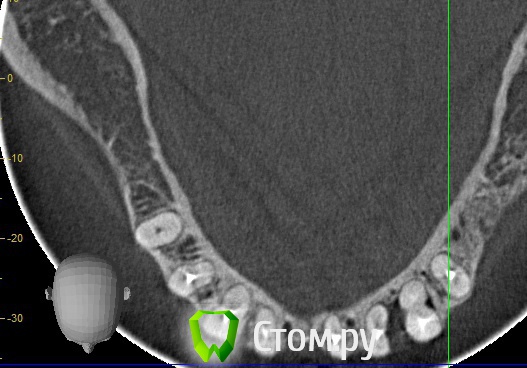

stradalitca Опубликовано 29 мая, 2014 Автор Поделиться Опубликовано 29 мая, 2014 Всем добрый вечер! у меня есть новая информация по поводу перфорированной тройки снизу слева. я ещё раз досканально просмотрела. Оказывается она пробита не ровно между отростками корня, там всё цело. а пробит по сути один отросток корня. Может ещё не поздно закрыть чем-либо эту перфорацию? что скажете( штифт поставили примерно 15-20 декабря)? Ссылка на комментарий

Korel Опубликовано 6 июня, 2014 Поделиться Опубликовано 6 июня, 2014 всем добрый вечер! А если рассматривать бюгельный протез, то надо будет вовлекать правую восьмёрку и одевать на ней коронку?я совсем запуталась... Не на одном срезе не нашёл апекс 48 , надо сначала посмотреть его, затем снять мост, оценить коронкОвую часть, подвижность и проч. Если всё Ок, то запараллелить, закрыть литьём и кмк можно использовать. Конечно надо смотреть очно. Ссылка на комментарий